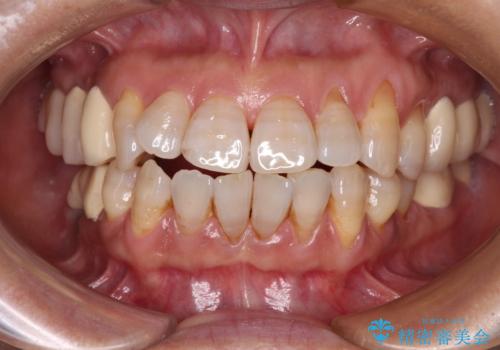

治療後に歯茎から出血 インプラントとオールセラミッククラウンの補綴治療

- 治療をおこなって以来、クラウン周りの歯肉から出血が続くとのことで来院された患者様です。

診察を行ったところ、クラウンと歯の境目が不適合で汚れが溜まりやすく、炎症を起こしている状態でした。

治療を終えたばかりですが、出血を改善するためには作り直しが必要と判断し、オールセラミッククラウンにて補綴治療することとしました。